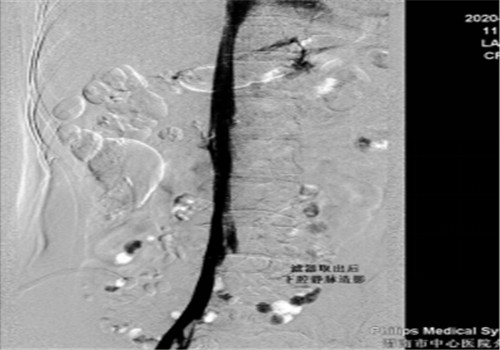

8月中旬患者来院复查,顺利骨取出科钢板,右下肢未见深静脉血栓,于8月14日行下腔静脉滤器取出术,手术顺利,历时30分钟。

据介入科李建国主任介绍,患者血管介入治疗采用了新型的可回收滤器,是目前最新的治疗手段,有着无可比拟的优势,减少肺栓塞猝死并发症的同时、解决了患者终生服用抗凝药的烦恼,亦避免了滤器长期置入体内而出现的并发症。此项手术的成功实施可使渭南区域内广大深静脉血栓患者终生受益。